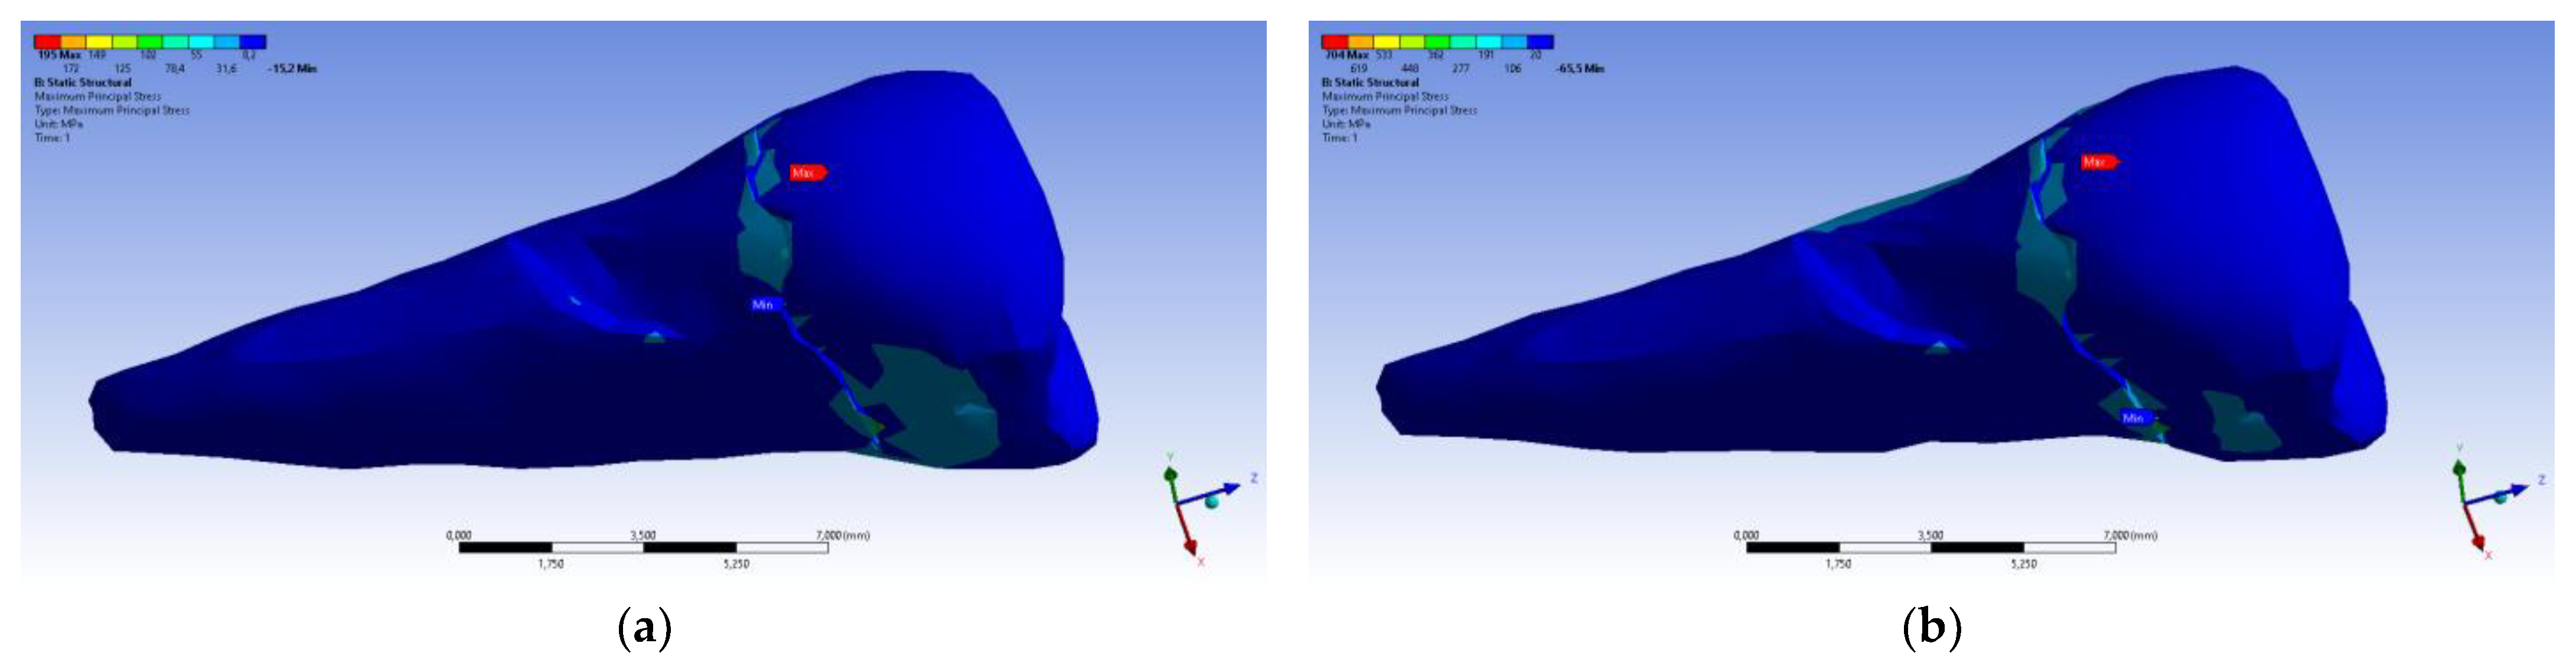

| Total Deformation | Deformation in X Direction | Deformation in Y Direction | Deformation in Z Direction | Equivalent Stress | Normal Stress X | Normal Stress Y | Normal Stress Z | Maximum Main Stress | Minimum Main Stress | Tangential Stress XY | Tangential Stress YZ | Tangential Stress XZ | |

|---|---|---|---|---|---|---|---|---|---|---|---|---|---|

| Minimum | 0 mm | −4.24 × 10−3 mm | −2.52 × 10−2 mm | −1.56 × 10−2 mm | 1.01 × 10−6 MPa | −35.6 MPa | −57.1 MPa | −104 MPa | −15.2 MPa | −152 MPa | −43.7 MPa | −39.6 MPa | −56.3 MPa |

| Maximum | 2.77 × 10−2 mm | 3.57 × 10−3 mm | 6.98 × 10−4 mm | 4.78 × 10−3 mm | 248 MPa | 61.5 MPa | 177 MPa | 72.2 MPa | 195 MPa | 21.4 MPa | 44.2 MPa | 117 MPa | 22.2 MPa |

| Minim. in | Cementum | Cementum | Enamel | Enamel | Cementum | Cementum | Enamel | Enamel | Enamel | Cementum | Enamel | Enamel | Cementum |

| Maxim. in | Enamel | Enamel | Cementum | Enamel | Cementum | Enamel | Enamel | Enamel | Enamel | Enamel | Cementum | Cementum | Cementum |

| Total Deformation | Deformation in X Direction | Deformation in Y Direction | Deformation in Z Direction | Equivalent Stress | Normal Stress X | Normal Stress Y | Normal Stress Z | Maximum Main Stress | Minimum Main Stress | Tangential Stress XY | Tangential Stress YZ | Tangential Stress XZ | |

|---|---|---|---|---|---|---|---|---|---|---|---|---|---|

| Minimum | 0 mm | −6.1 × 10−3 mm | −9.02 × 10−2 mm | −3.99 × 10−2 mm | 1.02 × 10−6 MPa | −112 MPa | −199 MPa | −278 MPa | −65.5 MPa | −470 MPa | −148 MPa | −176 MPa | −178 MPa |

| Maximum | 9.28 × 10−2 mm | 1.83 × 10−2 mm | 1.38 × 10−3 mm | 3.12 × 10−2 mm | 780 MPa | 61.5 MPa | 649 MPa | 304 MPa | 704 MPa | 73.8 MPa | 134 MPa | 370 MPa | 78.6 MPa |

| Minim. in | Cementum | Cementum | Enamel | Enamel | Cementum | Cementum | Enamel | Enamel | Enamel | Cementum | Enamel | Enamel | Cementum |

| Maxim. in | Enamel | Enamel | Cementum | Enamel | Cementum | Enamel | Enamel | Enamel | Enamel | Enamel | Cementum | Cementum | Cementum |